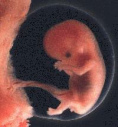

Sogar Feten [Föten] und Säuglinge sind in Leber und Nieren

bzw. in Gehirn und Nieren als Folge von Amalgamfüllungen

der Mutter bereits quecksilberbelastet (Drasch et al.

1994). Das Ausmass dieser fetalen bzw. frühkindlichen

amalgambedingten Quecksilberbelastung ist gravierend:

Babys (im Alter von 11 - 50 Wochen) von Müttern mit mehr

als 10 Amalgamfüllungen wiesen - in Korrelation mit dem

Amalgamstatus der Mütter - Werte von bis zu

2.543,8 µg Hg / kg

Nierengewebe

(Feuchtgewicht, so auch bei den folgenden Gewichtsangaben)

auf. Diese amalgambedingte Quecksilber-Konzentration liegt

weit über dem von Drasch et al. (1992) bei einem

Gesamtkollektiv von 166

Erwachsenen festgestellten

Spitzenwert (1.598,0 µg Hg / kg Nierengewebe). Die von

Schiele et al. (1981) bei 51 Verstorbenen im Alter

zwischen 10 und 100 Jahren in den Nieren gemessenen

Spitzenwerte von bis zu 801 µg Hg / kg Nierengewebe werden

als Folge von Amalgamfüllungen der Mütter bei Babys z.T.

um mehr als das 3fache überschritten. auch die bei

Verstorbenen nach einem Berufsleben als

Zahnarzt in

den Nieren vorgefundenen Hg-Werte - bis zu 2.110 µg Hg /

kg Nierengewebe (Nylander et al. 1989) - liegen noch

deutlich unter den bei Babys amalgambehandelter Mütter

ermittelten Quecksilber-Konzentrationen in den Nieren.

Sogar ein Teil der von Kosta et al. (1975) untersuchten

Quecksilber-Bergarbeiter

hatte eine niedrigere Hg-Belastung in den Nieren (2.300 µg

Hg / kg Nierengewebe), als sie durch Amalgamfüllungen der

Mütter im Nierengewebe der Babys verursacht werden kann.

Babys (11 - 50 Wochen) von Müttern mit 0 - lediglich 2

Amalgamfüllungen wiesen in der Studie von Drasch et al.

(1994) einen Spitzenwert von 75,9 µg Hg / kg Nierengewebe

(S.70)

auf. Mit Zunahme der Zahl der Amalgamfüllungen der Mütter

auf über 10 steigt der Quecksilbergehalt (Spitzenwert) in

den Nieren von Baby also auf mehr als das 30fache.